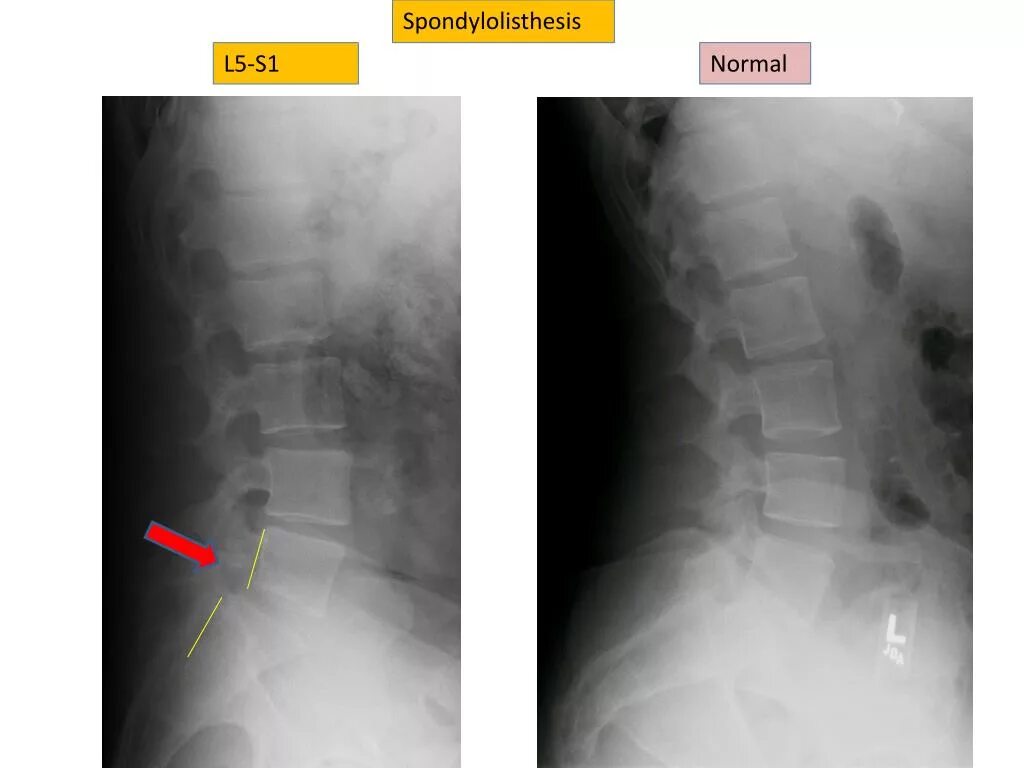

Смещение 5